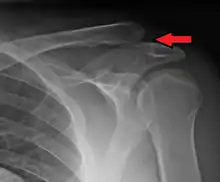

| An Xray showing a separated shoulder. Notice the separation between the end of the collarbone and the scapula. | |

X-ray indicates a separated shoulder when the acromioclavicular joint space is widened (it is normally 5 to 8 mm).[8]